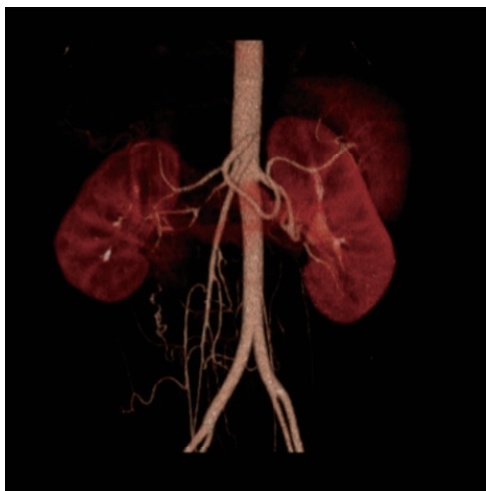

年轻女性,重度高血压伴低血钾

病史摘要:患者为 21 岁女性,1 天前因头晕测血压发现重度升高,无其他不适。1 个月前有上呼吸道感染症状,后出现颌下淋巴结肿大。既往体健,无慢性疾病、传染病、手术外伤等病史,月经规律。家族中外祖母有高血压,否认一级亲属高血压及其他遗传性疾病史。 诊疗过程:入院查体无明显异常体征。辅助检查提示血钾低,醛固酮、肾素活性增高,尿蛋白微量。肾脏、肾上腺等超声部分未见明显异常,眼底为 I

右肾动脉狭窄

肾血管性高血压